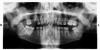

Dr. Stom Опубликовано 29 декабря, 2009 Поделиться Опубликовано 29 декабря, 2009 Здравствуйте, уважаемые специалисты! Проинтерпретируйте, пожалуйста, мой снимок. Очень бы хотелось услышать компетентное мнение, так как по собственным ощущениям проблемы есть, но вот где, какие и насколько они серьезны хочется выяснить.Буду очень признателен! отсутсвует 6 справа ввреху, это первая проблема, рядом 15 сильно разрушен может и удаление светит по причине невозможности адекватно востановить, 14,13 возможен кариес надо смотреть...в 24 нужно в каналы лезть и смотреть 25 проверьте на кариес отсутствие 26 проблема причем места для протезирования нет нужна ортодонтия...37 кариес отсутствует 37 проблема 35, 34 возможны кариесы надо смотреть...44,45 возможен кариес надо смотреть 46 отсутствует тоже проблема. одним словом работы много и надо этим заниматься решиний может быть куча и всё индивидуально.С Наступающим! Ссылка на комментарий

Aleksandr (Moscow) Опубликовано 30 декабря, 2009 Автор Поделиться Опубликовано 30 декабря, 2009 Большое спасибо. И Вас с наступающим! Буду потихоньку эти проблемы решать. Еще вот что.. А есть ли на снимке проблемы, требующие немедленного решения? Какие-нибудь воспаления, кисты и пр. И еще вопрос-что это за два темных круглых пятна вверху над зубами (слева и справа), а также прямо под носом? Особенно интересует левая часть, так как именно в том районе сильная боль и легкая припухлость щеки (по собственным ощущениям). Ссылка на комментарий

Bier Опубликовано 31 декабря, 2009 Поделиться Опубликовано 31 декабря, 2009 удалять 15й зуб а болит наверное из-за периодонтита в 24 зубе Ссылка на комментарий